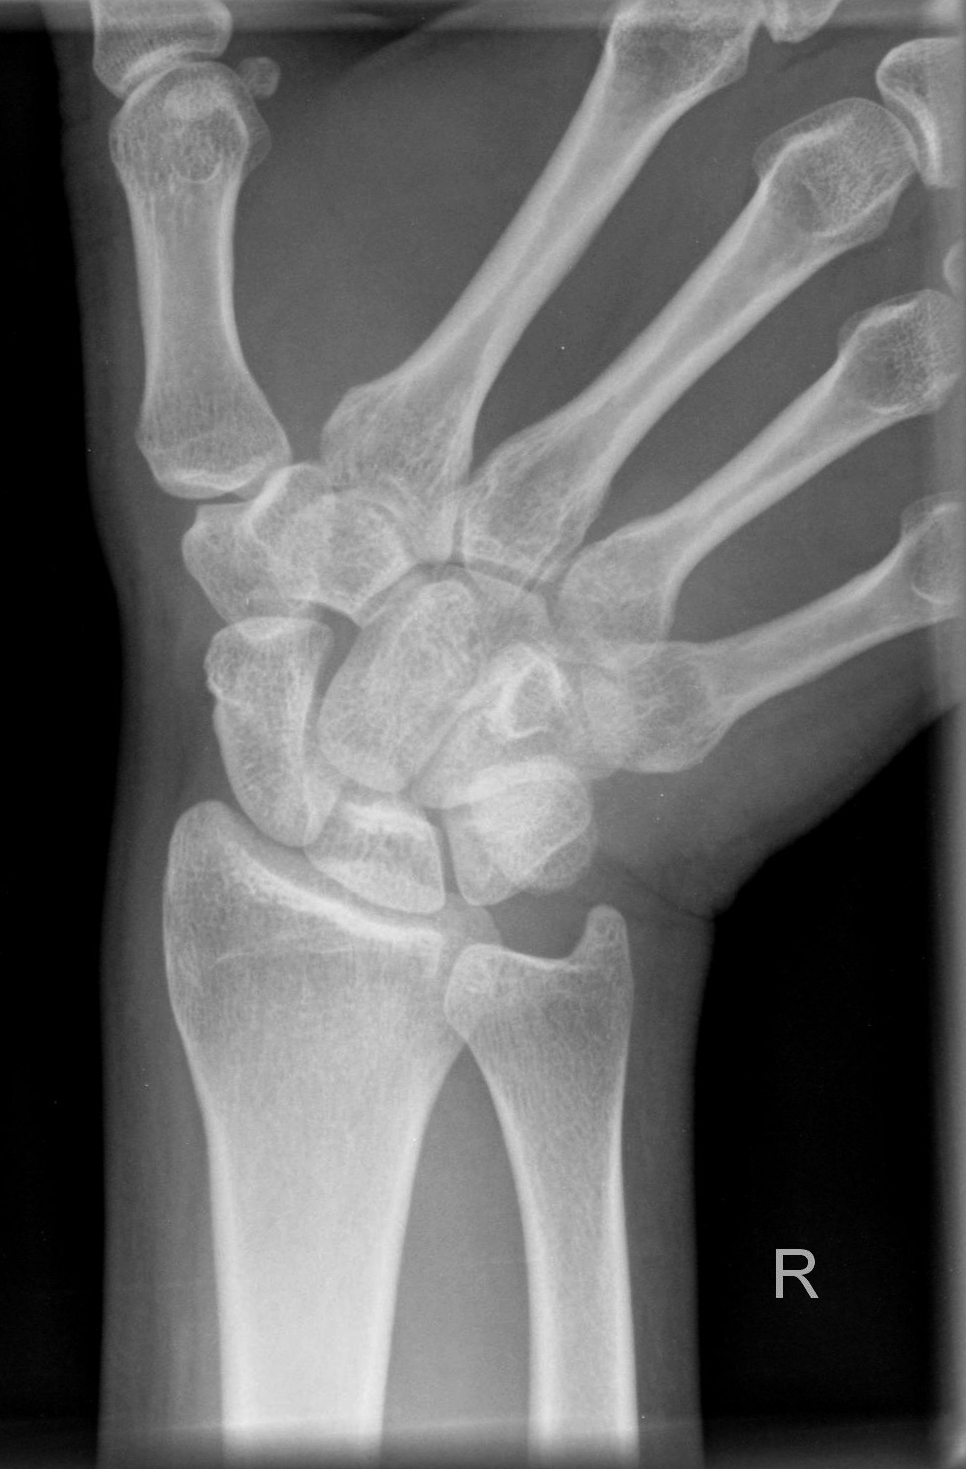

Os scaphoideum (Quartettaufnahme - Spezialaufnahme)

Technik

Lagerung

1.    Aufnahme

HG/Hand liegt flach auf

Hand kräftig bzw. so weit wie möglich zur Kleinfingerseite abduzieren

Daumen und Radius bilden eine Linie

2.    Aufnahme

15° Keil unter Bildempfänger

Lagerung siehe 1. Aufnahme

3.    Aufnahme

Unterarm und Hand an der radialen Seite um ca. 45° anheben

dabei ruhen die Finger auf der abfallenden Seite des kleinen 45° Keil

4.    Aufnahme

Unterarm und Hand an der ulnarer Seite um ca. 45° anheben

den Unterarm nicht anheben

dabei ruhen die Finger auf der aufsteigenden Fläche des kleinen 45° Keil

Zentralstrahl

1.- 4. Aufnahme

Längszentrierung: 1QF von der Hautgrenze zu den Handwurzelknochen

Querzentrierung: Kuhle distal von Proc. Styloideus radii

Einblendung

2QF in alle Richtungen

Bemerkung

Os scaphoideum: zwischen Daumensattelgelenk und Radius

Bei Kassette: es empfiehlt sich im Uhrzeigersinn auf der Kassette zu arbeiten.

Qualitätskriterien

Os scaphoideum soll orthograd überlagerungsfrei abgebildet sein, in den Schrägaufnahmen weitgehend überlagerungsfreie Darstellung des Os scaphoideum und der angrenzenden Handwurzelknochen. Schwer erkennbare Brüche sind oft nur in diesen Schrägaufnahmen diagnostizierbar.